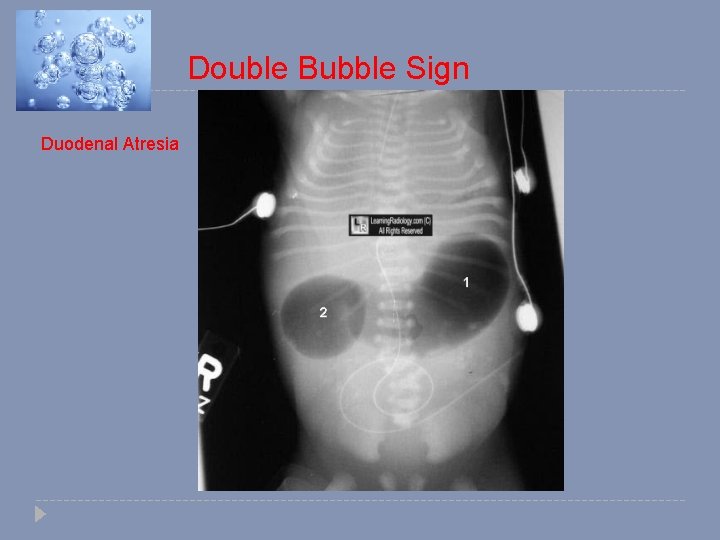

Double Bubble Sign Duodenal Atresia